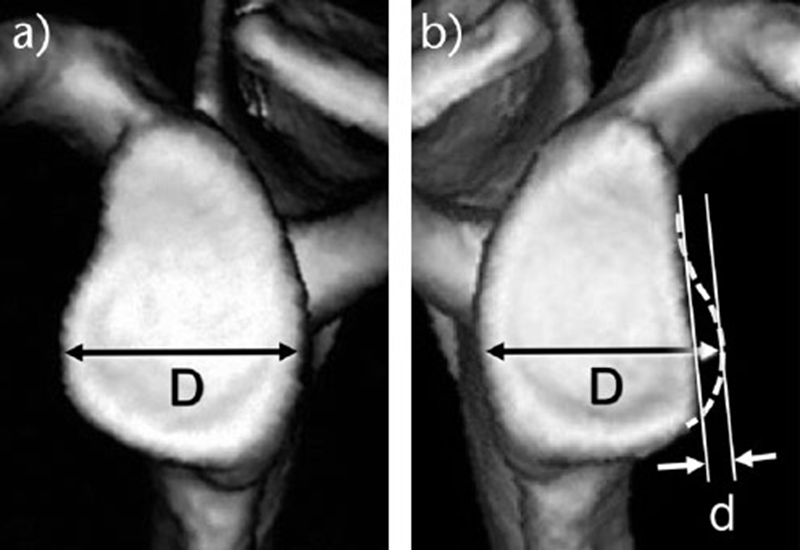

关节盂缺损的程度用什么方法表达呢?有面积测量和线性测量两种方法,目前主流应用的是面积测量法,以后文章会讲到轨道上/轨道外(On-track and of-track)的概念,也是应用这种方法测量缺损的。

线形测量:a)对侧关节盂,完好无损。D代表完整的肩胛盂的宽度;

b)患侧的肩胛盂骨质缺损。D来自完整侧,完整的肾盂宽度D与缺损的肾盂宽度之间的差值为缺损宽度d。缺陷的大小表示为d/D×100(%)。